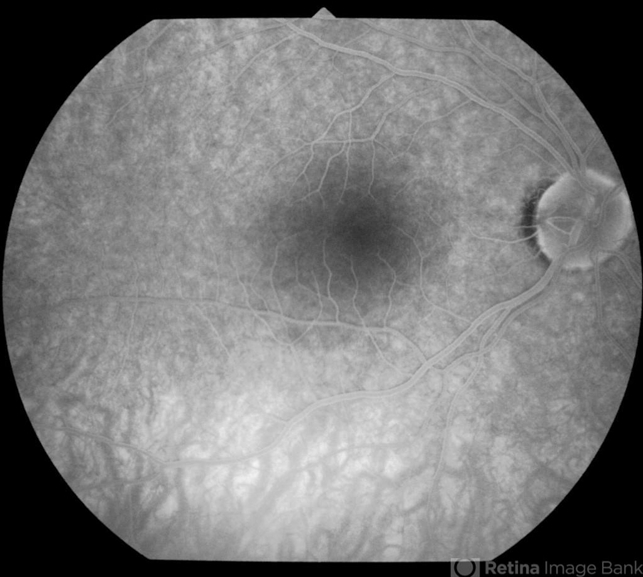

- optic pit, fluorescein angiogram (FA)

- Fundus photograph of 38-year-old healthy man with right optic disc pit, who recently noticed slightly blurred vision in right eye while closing the left eye. BCVA was 20/25 in OD and 20/20 in OS. IOP was 15mmHg OD and 14 mmHg OS. Right fundus exam showed small optic disc pit near the temporal rim of optic disc with abnormal reflex of nasal macula. Left fundus was normal. Late FA of right optic disc showed no leakage or staining of optic disc. Macular OCT showed normal foveal contour with no subretinal fluid or macular edema. There was significant reduction in RNFL thickness in the temporal sector in right eye. Coloboma is clearly seen on vertical OCT scan as well as horizontal scans through right optic pit.